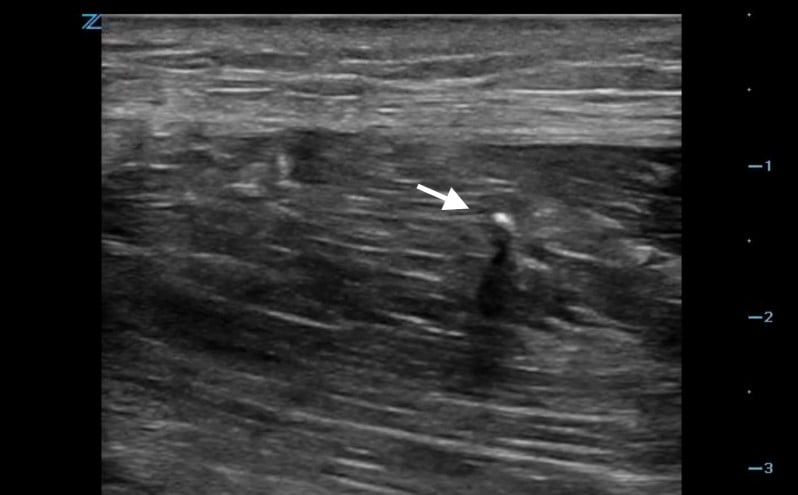

- Metal objects tend to produce reverberation, comet tail artifacts or acoustic shadows (Video 5).

- Figure 3. Reverberation from metal foreign body

- Figure 4. Comet tail artifact from metal foreign body